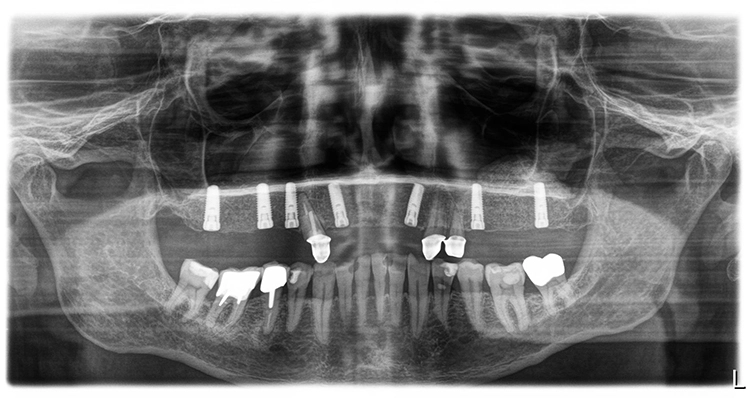

Der Therapieplan wurde in Abstimmung mit dem Patienten erstellt. Dabei war zu berücksichtigen, dass der Patient über den gesamten Behandlungszeitraum bis zur Fertigstellung der definitiven Restauration unbedingt kaufunktionell versorgt zu bleiben wünschte, da er zwischenzeitlich in Campingurlaub gehen wollte. Aufgrund der starken Pneumatisation der Kieferhöhlen wurden im posterioren Bereich beidseitig ein externer Sinuslift und nach Ausheilung der Strukturen die Implantation von sieben Implantaten (Conelog, Camlog, Wimsheim) mit unterschiedlichem Durchmesser und je 13 mm Länge geplant.

Die Implantatmaße und -positionen sowie der Umfang der Sinusbodenelevation wurden dabei in Sinne eines „backward planning“ anhand von DVT-Aufnahmen bestimmt. Zahn 13 sollte noch vorübergehend erhalten bleiben, um zusammen mit den bleibenden Zähnen 23 und dem entsprechend kariesbehandelten Zahn 24 bis zur Fertigstellung der definitiven Restauration der alten Teleskopprothese als Interimsersatz Halt zu geben. Als definitive Versorgung wurden drei VMK-Brücken auf NEM-Gerüsten vorgesehen. Damit sollte auch die natürliche Bezahnung im Unterkiefer von 37 bis 47 abgestützt werden.

Der aus der DVT-Aufnahme ersichtliche starke Höhendefekt beidseits machte einen externen Sinuslift notwendig, um Implantate mit optimaler Länge setzen zu können. Das Verfahren der lateralen Antrostomie weist eine hohe Sicherheit auf. So werden die Überlebensraten der Implantate beim externen Sinuslift und einzeitiger Operation mit 88,5 % und bei zweizeitigem Vorgehen mit 90,9 % angegeben [5,8].

Nach einer – aufgrund eines Campingurlaubs von sechs auf acht Monaten – verlängerten Heilphase konnte der Patient implantiert werden. In der Röntgenkontrollaufnahme zeigten sich stabile knöcherne Strukturen in den augmentierten Bereichen des Sinus. Die Insertionen erfolgte gemäß Protokoll frei Hand auf Grundlage der DVT-Aufnahme und orientiert an der alten Teleskopprothese.